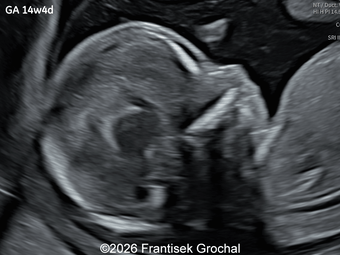

A 35-year-old secundigravida was referred to our unit at 20 weeks gestation for evaluation of suspected fetal skeletal abnormalities. Her first child was healthy, and her personal and family history were otherwise unremarkable. Two years later in a subsequent pregnancy, the patient presented for ultrasound evaluation. This examination was performed at 13 weeks of gestation and demonstrated the following findings: